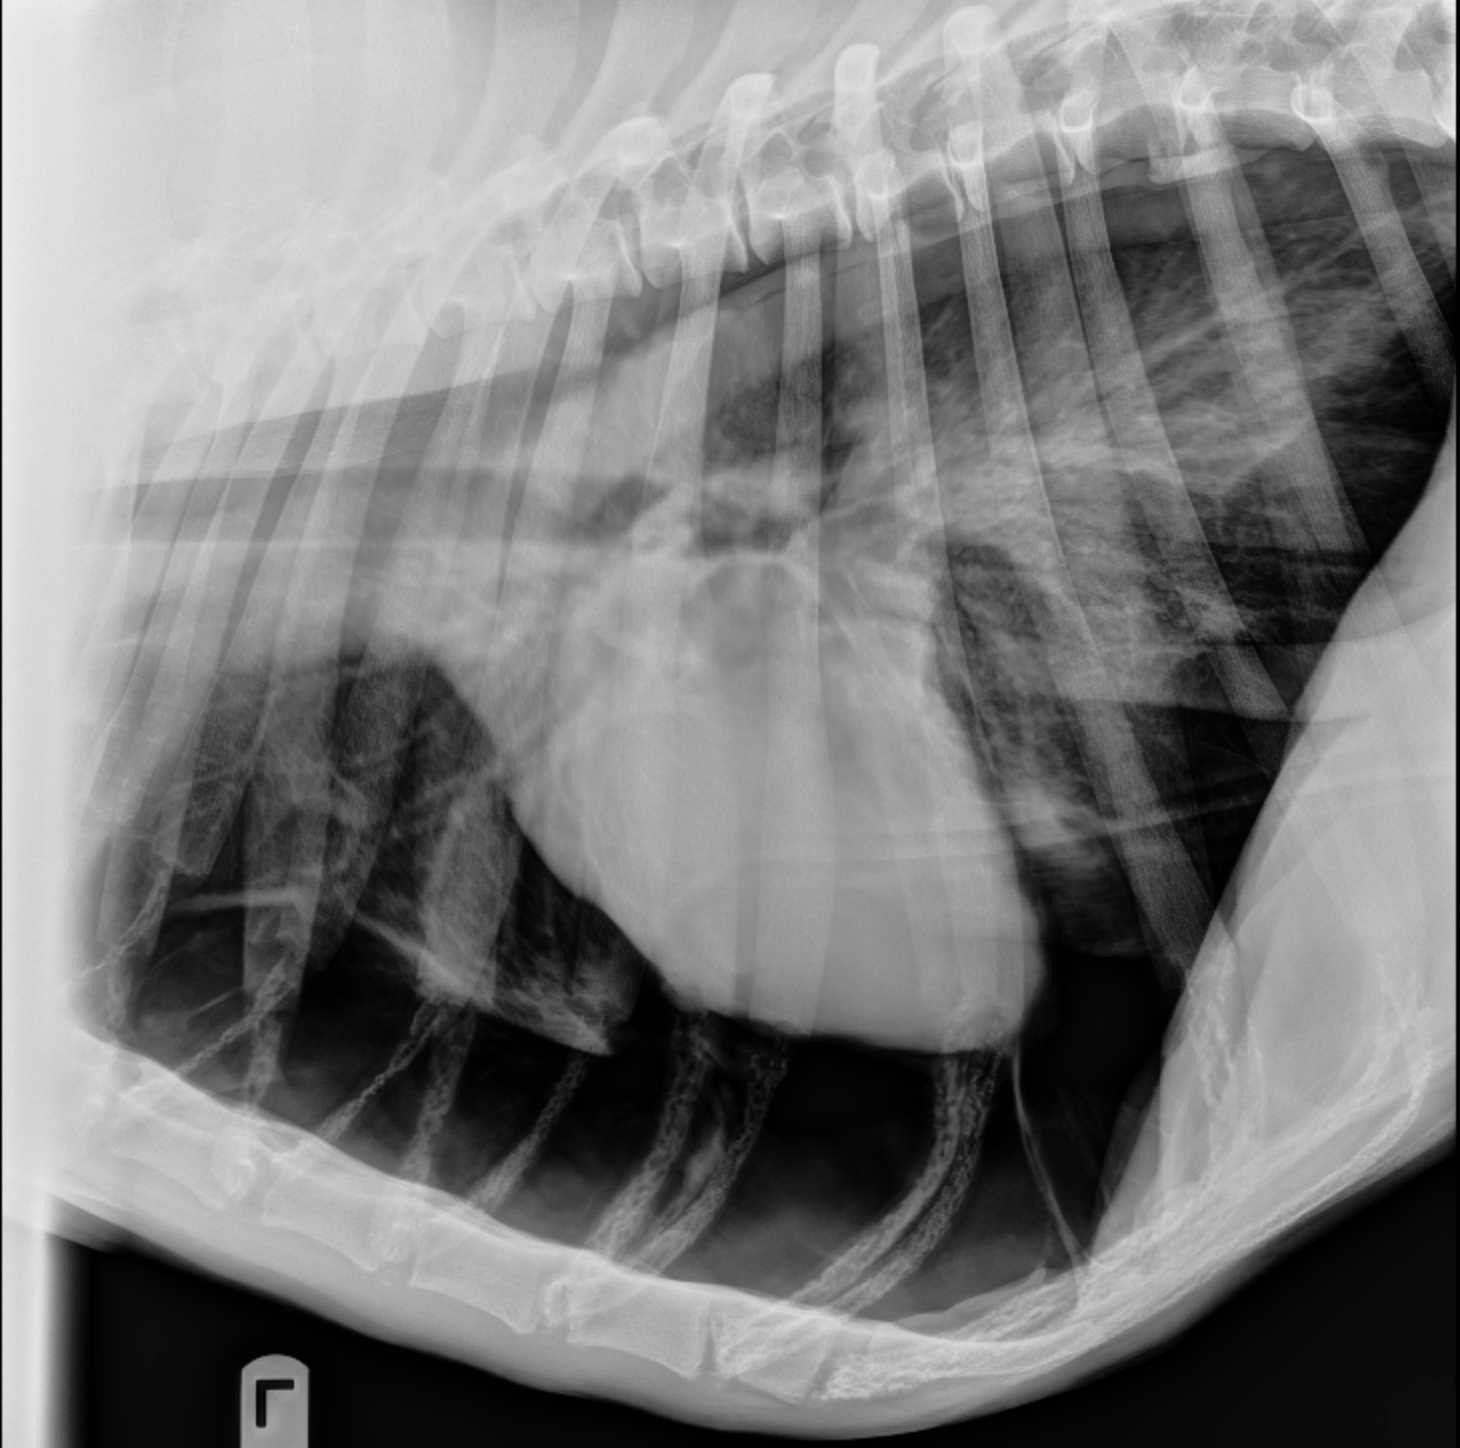

Thoracic Radiology in the Diagnosis of Congenital Heart Disease in Dogs How Much Is Chest X Ray For Dog However, the range can be between $75 and $500, depending on numerous factors. This ensures your veterinarian can see all sides of the structures inside your pet’s body. There is a wide price range for a few reasons, so let’s break down these factors below. The heart muscle is denser, while. How Much Is Chest X Ray For Dog.